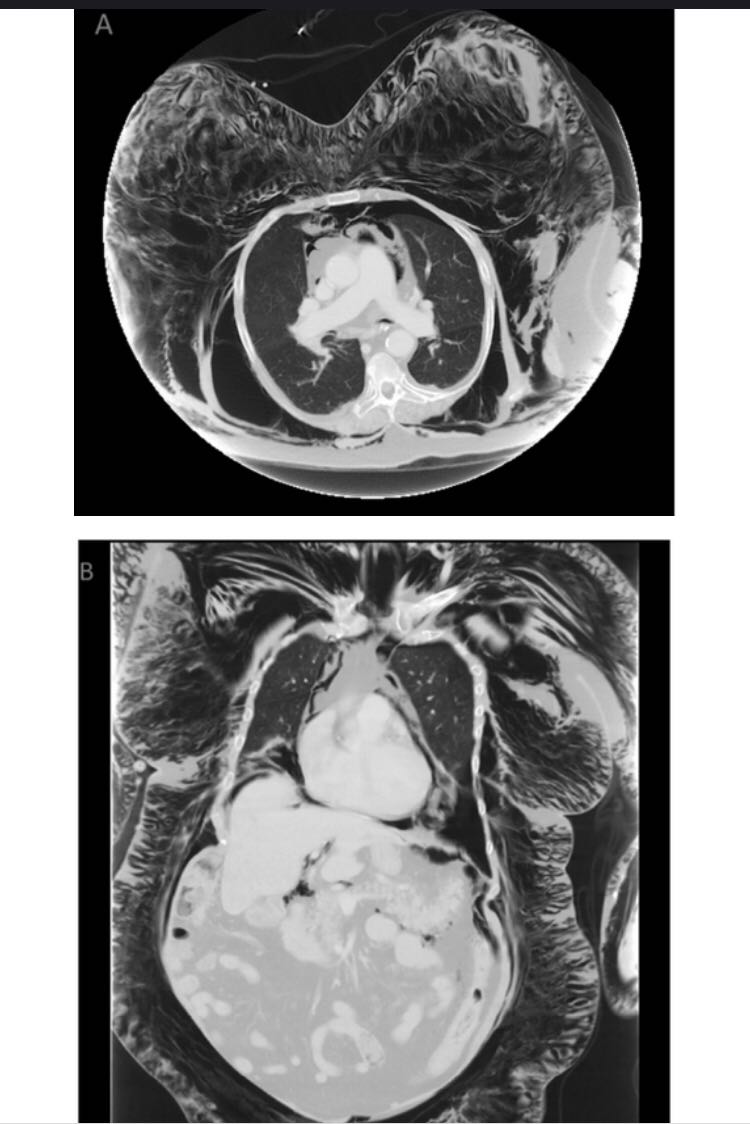

体格检查显示,患者意识不清,面部、颈部、躯干和肢体都有明显的肿胀和捻发音。胸腹及盆腔CT(图A和B)显示弥漫性皮下气肿,纵隔积气和左侧气胸。需行紧急气管切开术,确诊气管后壁裂并进行修补。2天后,尽管患者接受了机械通气,但皮下气肿自行消失。

诊断:气管穿孔后弥漫性皮下气肿 予紧急气管切开引流气体后,好转